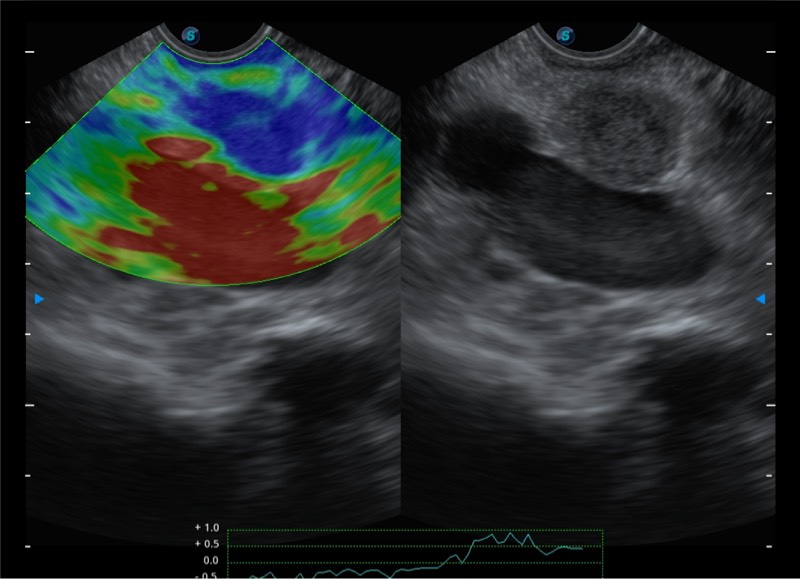

基于二十年的超声技术积累,玖鼎集团提供了最新一代的独立超声主机,在提供高质量图像的同时满足多学科使用。具备常见多普勒技术并提供弹性成像、声学造影等高端影像技术。新一代传感器具有更强的抗干扰能力并减少图像伪影。

• 4-12MHZ宽频输出